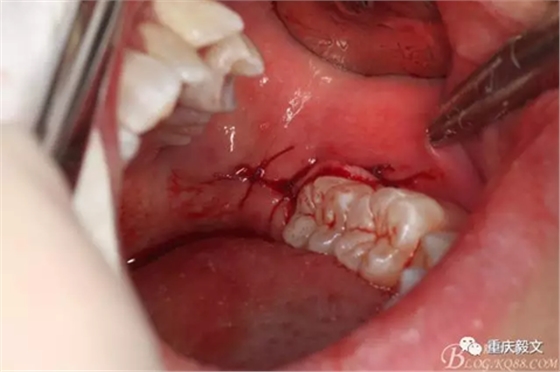

圖9.拔除后的38牙槽窩。牙槽窩的處理:去除過(guò)銳的骨尖骨緣,及碎骨片和碎牙片,復(fù)位牙槽窩。如牙槽窩損傷較大,為防止發(fā)生干槽癥,可在拔牙創(chuàng)內(nèi)放置少許碘仿紗條。這個(gè)病例不放碘仿紗條。

圖10.縫合。縫合牙齦切口。檢查無(wú)明顯出血,將牙齦切口對(duì)位后縫合。原則上不切不縫,若切必縫。即只要切開(kāi),就必須縫合。最后咬棉花或紗布止血。醫(yī)囑。必要時(shí),給予抗感染治療